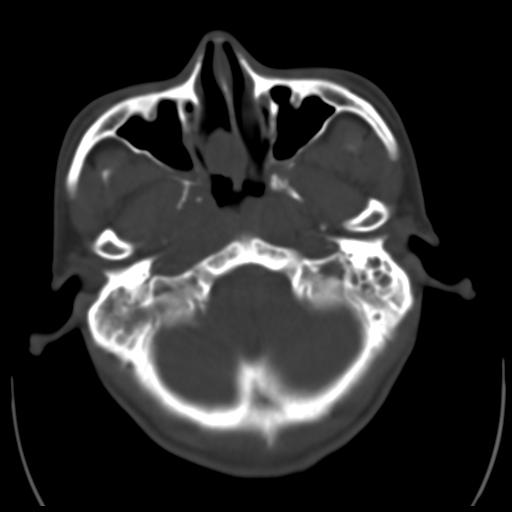

35m 鼻子时不时流血,头及右侧面部痛,颈部淋巴结未见明显大

软组织窗

考虑鼻咽癌侵犯颅底并突入右侧鼻腔;双侧中耳乳突炎。

蝶窦,后组筛窦及鼻咽部团块状软组织影,骨壁破坏,病变较广泛。考虑恶性肉芽肿。建议活检。

颅底骨质明显破坏 支持鼻咽癌 但病灶的边缘毛糙 不能除外炎性

蝶窦,后组筛窦及鼻咽部团块状软组织影,骨壁破坏,病变较广泛。考虑炎性肉芽肿性病变可能。建议活检。